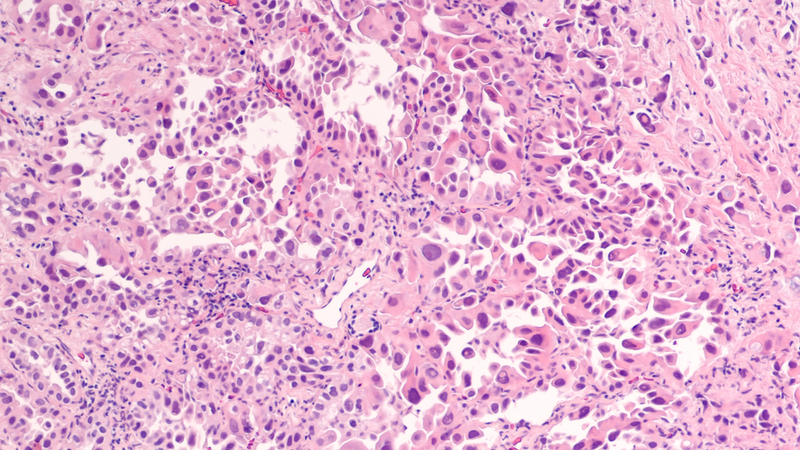

Scientists from the UK Department of Molecular and Cellular Biochemistry, led by Ramon Sun, PhD, and Matthew S. Gentry, PhD, have discovered that human non-small cell lung cancers accumulate nuclear glycogen during the formation of tumors, providing an opportunity to finally reveal the biological role of nuclear glycogen.

While nuclear glycogen accumulation has been reported in multiple cancers, this study demonstrates that glycogen is synthesized and broken down in the nucleus, that nuclear breakdown provides the fuel for histone modifications, and that these modifications allow cells to become cancerous. Non-small cell lung cancers suppress nuclear glycogen breakdown by decreasing the amount of a key signaling molecule called malin to drive cancer progression.